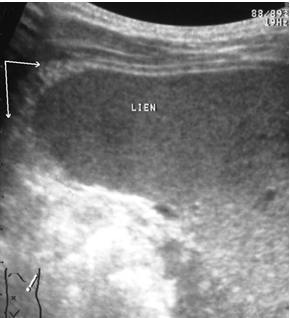

Чрескапсульные разрывы селезенки манифестируют нарушением непрерывности контура органа и визуализацией внутриорганных линий разрыва (рис. 7). Последние представляют собой гипоэхогенную или эхонегативную, в зависимости от времени, прошедшего после травмы, зону линейной или «ветвистой» формы с неровными и нечеткими контурами. Важно отметить, что прямые эхографические признаки, будучи патогномоничными для данного вида повреждений, не имеют облигатный характер. В частности, нарушение непрерывности контура селезенки наблюдается только у 25,4 % больных, а линия внутриорганного разрыва визуализируется в 60,3 % случаев. При этом возможность выявления указанных признаков в ранние сроки весьма проблематична и становится реальной только через 16–24 часа после травмы.

Рис. 7. Эхограмма чрескапсульного разрыва селезенки. Нарушение непрерывности контура указано стрелкой.

В связи с вышеизложенным особое клиническое значение приобретают косвенные эхографические признаки чрескапсульного разрыва органа, прежде всего внутрибрюшинного кровотечения, отмеченного у всех больных с таким характером травмы. Периспленическая гематома (рис. 8) представляет собой околоорганное скопление крови, полностью либо частично окружающее поврежденную селезенку и ограниченное такими анатомическими образованиями, как купол диафрагмы, задний листок париетальной брюшины, петли кишечника, фиксированные пряди большого сальника и т. д.

Следующим по значимости и частоте выявления косвенным эхографическим признаком чрескапсульного разрыва селезенки стала визуализация ткани большого сальника, фиксированного в зоне повреждения или окутывающего весь орган (рис. 9).

Рис. 9. Эхограмма чрескапсульного разрыва селезенки. Фиксированная прядь большого сальника указана стрелками.

Фрагментация (отрыв полюса) селезенки представляет, по сути, частный вариант чрескапсульного разрыва с полным разобщением фрагментов органа. Наряду с раздельной визуализацией фрагментов выявляются линии разрывов и вышеописанные косвенные признаки, характерные для данного вида повреждений (рис. 10).

Рис. 10. Эхограмма полного поперечного разрыва селезенки. Линия разрыва указана стрелками.